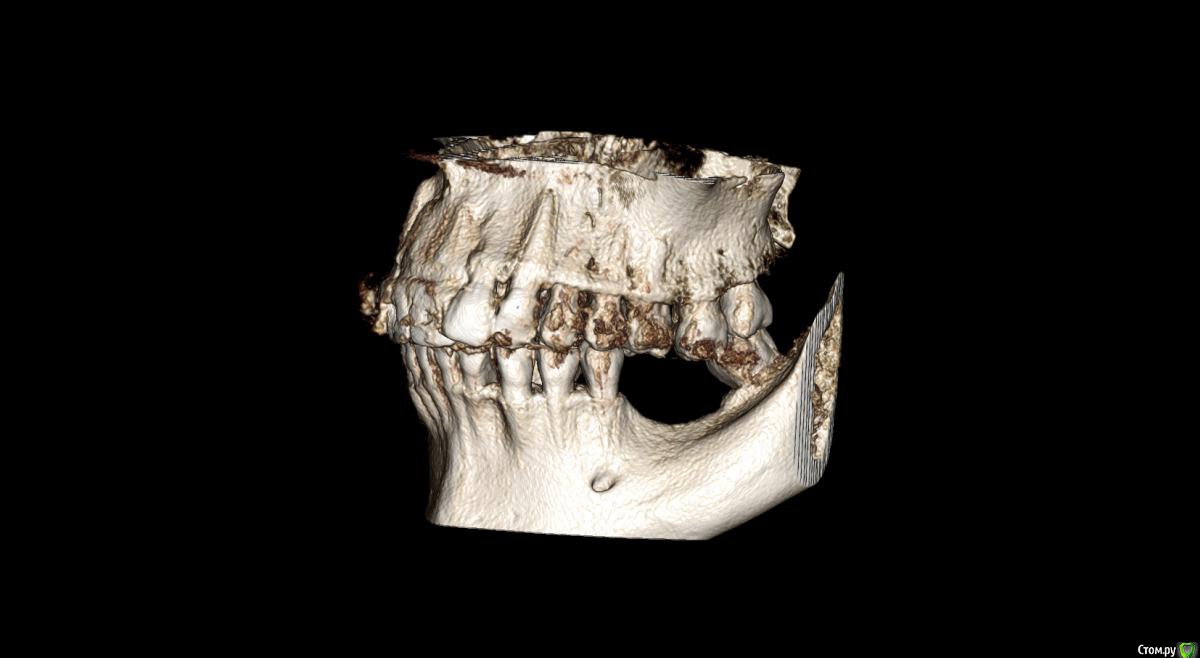

Господа как лучше тут поступить? поменьше бы рисков)

" всеводинэтап"крыша гаража" и латерализация отменяются)))

вижу вариант только с сеткой.

Из того что разобрал по срезам мне кажется можно медиально расщепить и притопить, дистально 4х6 поставить (астра, штрауманн...). Посмотрите, помещаются ли такие импланты. Травма меньше, быстрее и меньше рисков.

Сделайте нкр с медиальными болтами, дистальные глубже установите.

Тогда десну аля шашлычки и фдм отсроченно.

Далее временное протезирование.